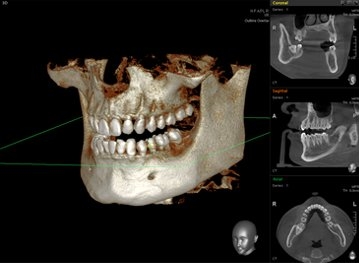

CT를 이용한 진단

CT를 통해 구강 전반은 물론 얼굴뼈 부위까지 광범위한 진단을 통해서 육안으로는 파악이 불가한 부분까지 볼 수 있습니다.

구강내의 구조나 뼈의 양, 상악동 수술여부 등 다양한 부분을 체크할 수 있어 의료진이 올바른 진단을 내리는데 도움을 줍니다.

CT진단을 활용하여 구강상태를 면밀하게 살펴보고 임플란트를 식립합니다.